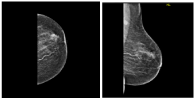

Figure 1. US: A non-vascular heterogeneous mass, slightly hypoechoic with micro lobulated borders at upper areolar margin that measures 15.10.15 mm BIRADS 4A.

Figure 2. MAM. left breast an irregular mass seen at upper anterior breast associated with ipsilateral suspicious lymph node, measures 20x17x17 mm, BIRADS 4C.

Figure 3. US: Left breast an irregular heterogeneous mass located at upper areolar margin, approximately 14x19

Figure 4. MAM. a small 1cm irregular micro lobulated & speculated mass at right upper inner with benign looking axillary nodes. BIRADS 5.